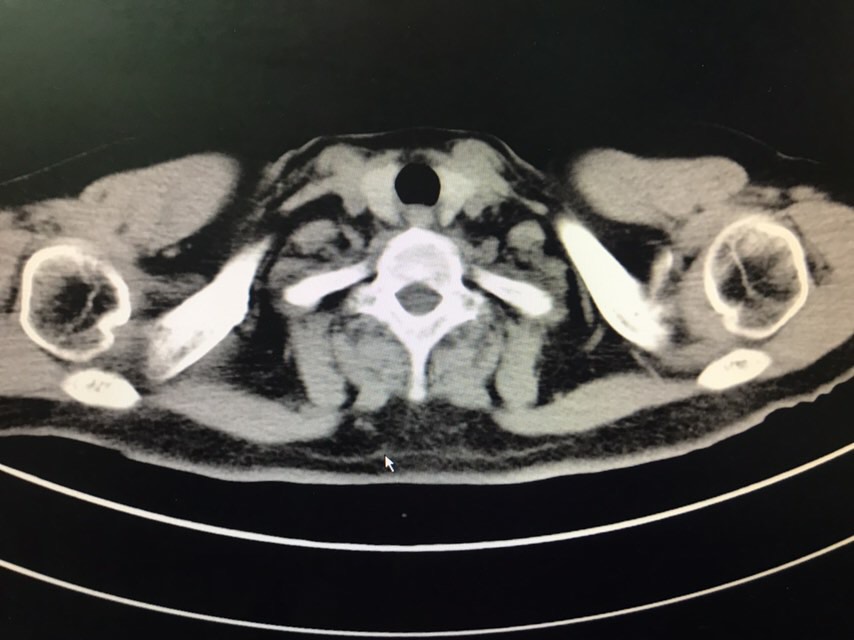

查体无特殊。辅助检查:PET-CT:1、部分颅骨、部分颅底骨质、双侧下颌骨、双侧肩胛骨、双侧锁骨、双侧肱骨上段、双侧多肋骨、胸骨、双侧髂骨、骶1棘突、双侧耻骨部分骨质虫蚀样、溶骨样破坏伴部分破坏骨质FDG代谢异常增高;上述改变考虑多发性骨髓瘤可能性大,请结合临床或右侧肋骨病灶活检。2、甲状腺右叶稍低密度结节影,无FDG代谢异常增高,多为良性病变,建议专科检查;3、双侧口咽壁对称性FDG增高,无确切占位征象,考虑为炎性改变;4、右肾错构瘤;5、脊柱部分骨质增生。骨髓涂片:目前BM示原始浆细胞比例增高8%,成熟红细胞呈缗钱状排列。骨髓活检:取材骨髓组织增生较低下,三系细胞增生均较低。骨髓流式:标本中若表达CD28,不表达CD19、CD117、cLambda、CD27、CD81、CD20、CD45,符合浆细胞肿瘤表型,正常浆细胞占有核细胞娥0.16%;流式检测中浆细胞易被破坏,比例可能低于形态学,请结合形态及免疫固定电泳结果。免疫球蛋白定量:IgG 12.6g/L,IgA 2.05g/L,IgM 0.94g/L,IgE 5.0g/L。血清固定电泳:未见IgG、IgA、IgM、KAP轻链、LAM轻链单克隆成分。尿固定电泳:在LAM区可见一条单克隆KAP轻链成分。血清游离轻链:游离KAP轻链 3800mg/L,游离LAM轻链16.00mg/L、游离KAP轻链/LAM轻链 237.5,尿游离轻链:游离LAM轻链 4100mg/L,游离LAM轻链9.13mg/L、游离KAP轻链/LAM轻链 449.069。